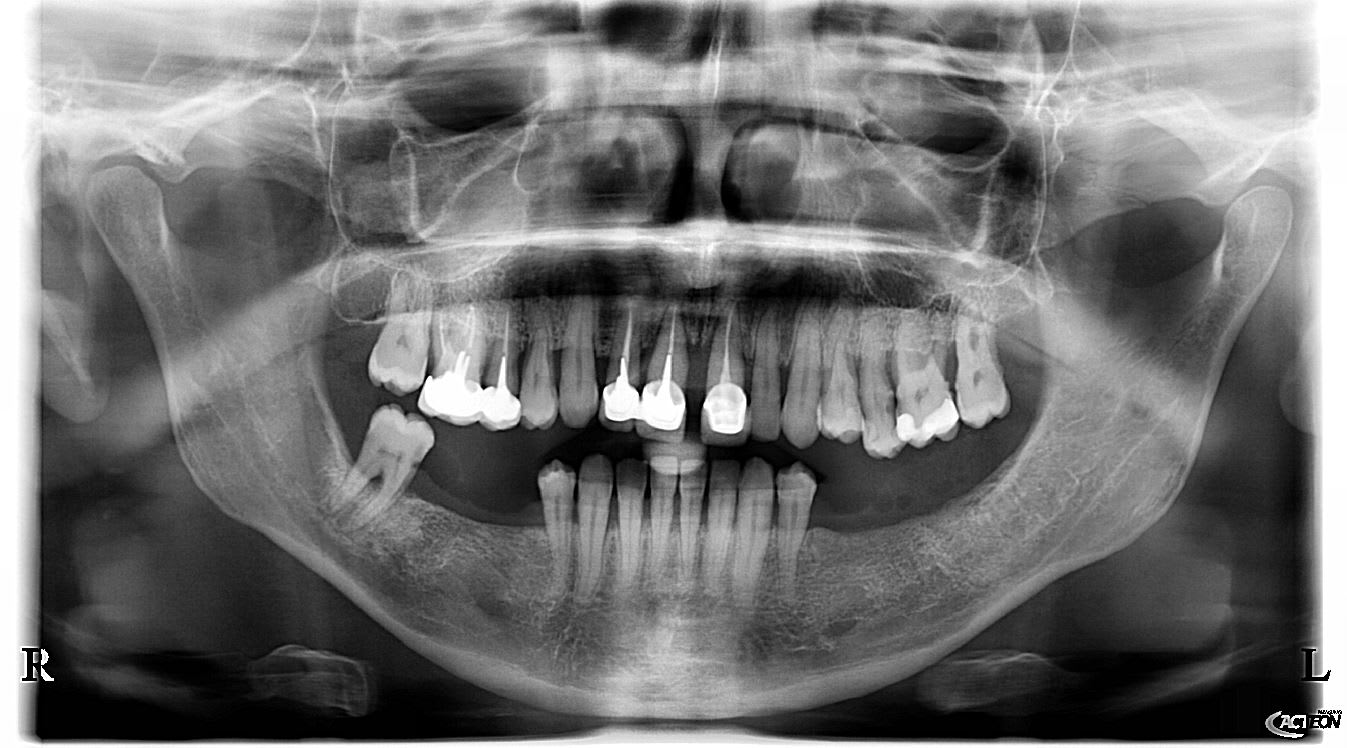

Patiente de 52 ans avec parodontite avancée

J'hésite pour le moment au niveau du plan de TTT puour la haut

mon plan de ttt est le suivant extraction les dents aboluments non conservable (11-21-25) et tenter de garder le reste, puis réévaluer le cas apres surfacage et gingivectomie. Puis de couronner le reste: bridge 13 12 (11 21) 23, couronnes jumélées 14 15 16 17, bridge 24 (25) 26 27.

Ou extraction totale haut, implantation immédiate et mise en charge immédiate (j'adresserai a un implanto pour cela)

Pour le bas ca me parait plus simple, soins 47, surafacage, implant 46 45 35 36 + cr

Ta pano Acteon : c'est une X Mind One ou déjà une X Mind Trium ?

c'est la trium CBCT...

La pano c'est effectivement la xmind trium de acteon